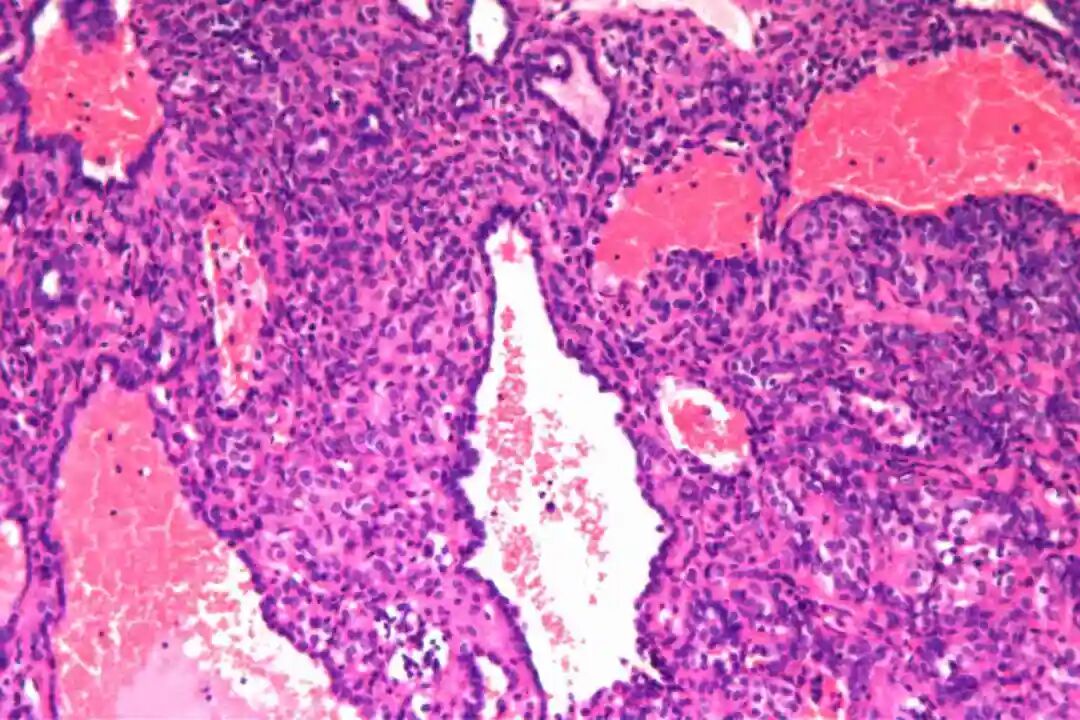

镜下特征:

细胞形态:两种独特的细胞类型,即表面立方细胞和间质圆形细胞。表面立方细胞通常呈立方形或低柱状,细胞核圆形或椭圆形,染色质细腻且分布均匀,核仁不明显或较小。细胞质丰富,呈嗜酸性,有时可见细小的颗粒状物质。间质圆形细胞则具有较大的核质比,细胞核多为圆形或卵圆形,染色质较深,核仁清晰可见。细胞质较少,呈淡嗜酸性或透明状,部分细胞可表现出一定的多形性。

组织特征:包括硬化区、出血区、实性区和乳头状区四种典型形式。硬化区由大量胶原纤维组成,其间散在分布着间质圆形细胞,这些细胞常围绕血管或呈片状排列。出血区则以红细胞积聚为特征,伴有泡沫状巨噬细胞和含铁血黄素沉积,周围可见表面立方细胞形成的血管样结构。实性区由密集的间质圆形细胞构成,细胞排列成片状或巢状,其间可见少量表面立方细胞覆盖的小管状结构。乳头状区最为复杂,其核心由纤维血管轴组成,表面被覆一层或多层表面立方细胞,周围环绕间质圆形细胞。这四种结构在肿瘤中往往以不同的比例混合存在,形成了PSP独特的病理景观。